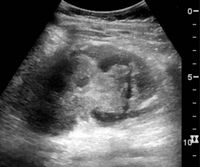

One of the primary indications for referral to US evaluation of the kidneys is evaluation of the urinary collecting system. Enlargement of the urinary collecting system is usually related to urinary obstruction and can include the pelvis, the calyces and the ureter. Hydronephrosis is seen as an anechoic fluid-filled interconnected space with enhancement within the renal sinus, and normally, the dilated pelvis can be differentiated from the dilated calyces.[1]

Several conditions can result in urinary obstruction. In both adults and children, masses, such as abscesses and tumors, can compress the ureter. In children, hydronephrosis can be caused by ureteropelvic junction obstruction, ectopic inserted ureter, primary megaureter and posterior urethral valve (Figure 13). In the latter, both kidneys will be affected. In adults, hydronephrosis can be caused by urolithiasis, obstructing the outlet of the renal pelvis or the ureter, and compression of the ureter from, e.g., pregnancy and retroperitoneal fibrosis. Urolithiasis is the most common cause of hydronephrosis in the adult patient and has a prevalence of 10%–15%.[1]

The hydronephrosis is typically graded visually and can be divided into five categories going from a slight expansion of the renal pelvis to end-stage hydronephrosis with cortical thinning (Figure 15). The evaluation of hydronephrosis can also include measures of calyces at the level of the neck in the longitudinal scan plane, of the dilated renal pelvis in the transverse scan plane and the cortical thickness, as explained previously (Figure 16 and Figure 17).[1]

Figure 15. End-stage hydronephrosis with cortical thinning. Measurement of pelvic dilatation on the US image is illustrated by ‘+’ and a dashed line.[1]